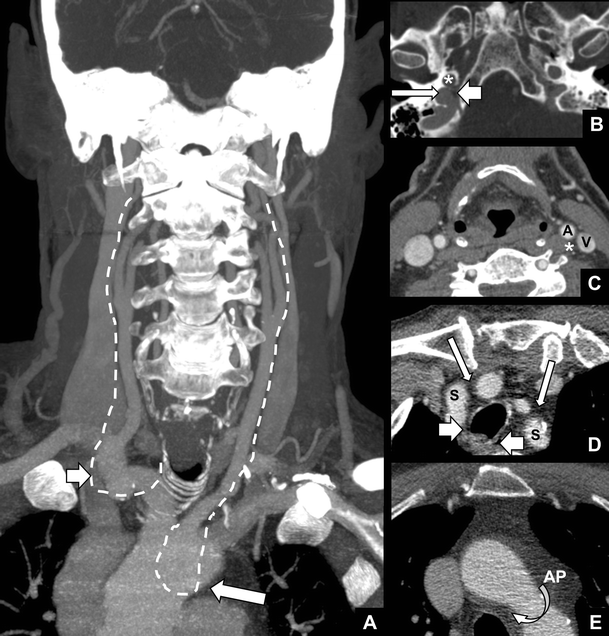

Vocal Cord Paralysis Anatomy Imaging And Pathology Insights Into Imaging Full Text

The Non Recurrent Laryngeal Nerve A Meta Analysis And Clinical Considerations Peerj